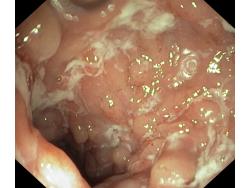

Choroba Leśniowskiego-Crohna